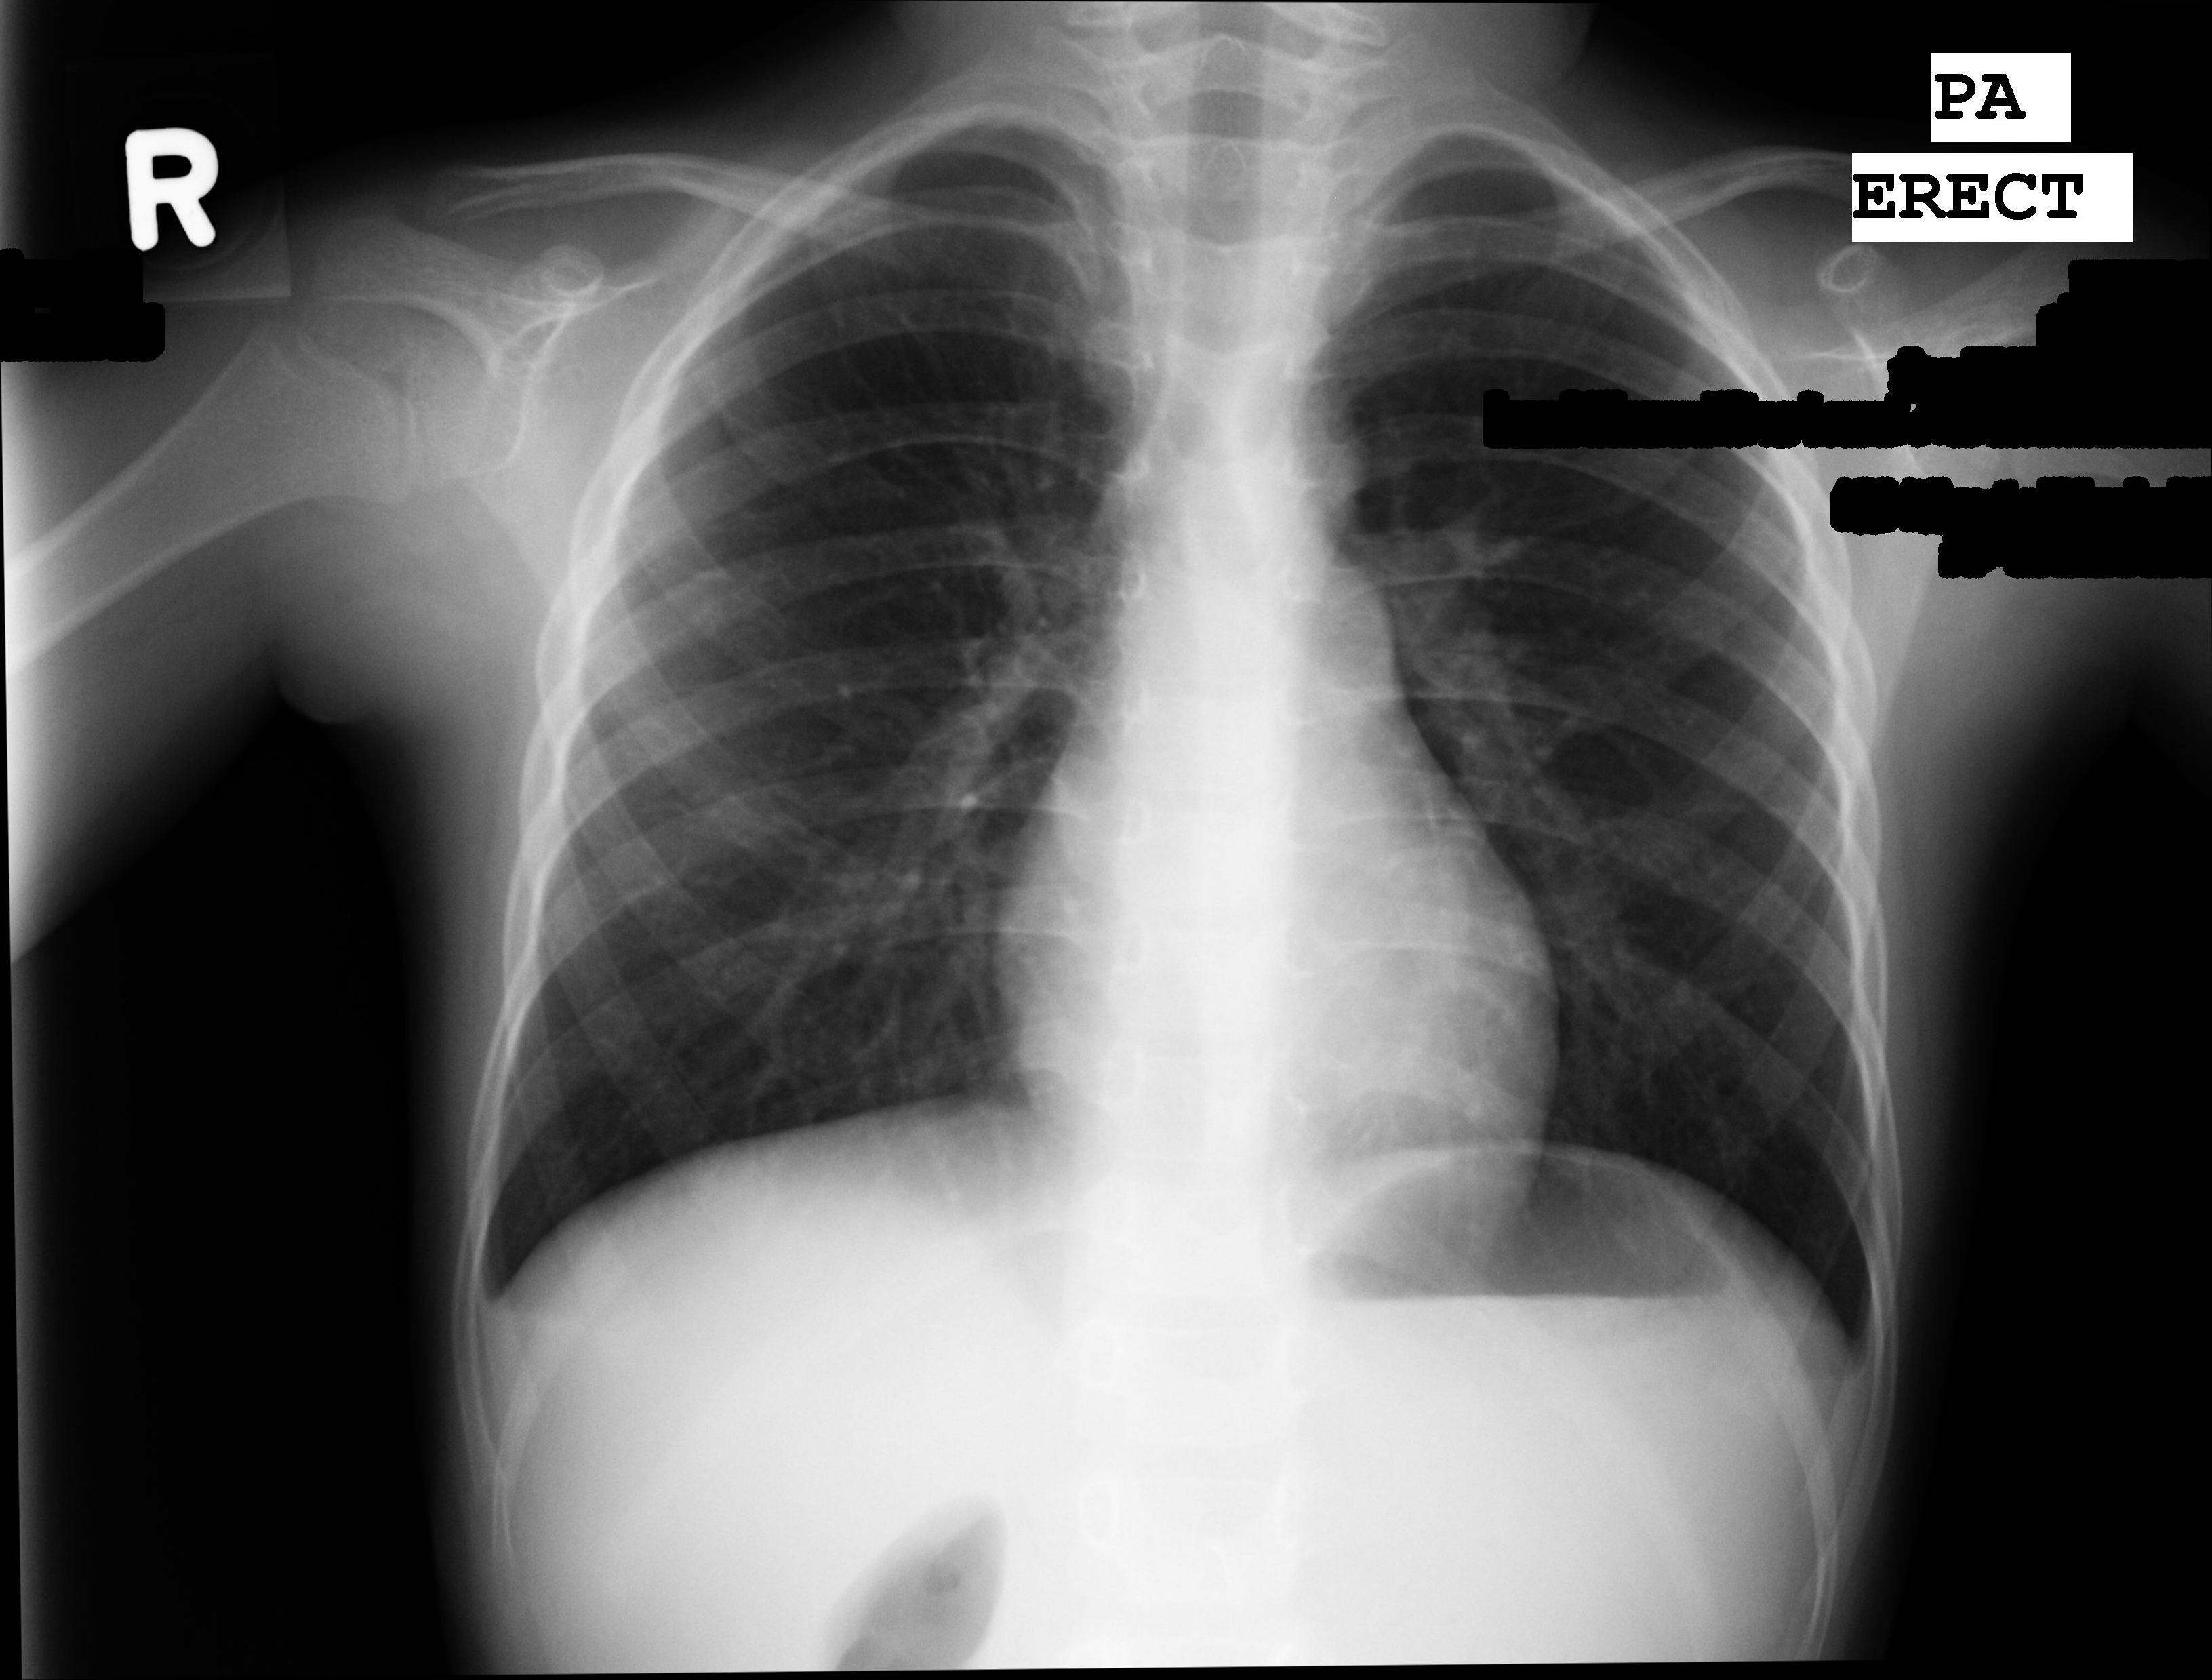

Once the text has been localized there are two possible options for removing it: image interpolation or masking. Image interpolation, or inpainting, is a magical tool in image processing where the image appears as if the text never existed, whereas masking is simply blanking out the image where the text used to appear. The choice between the two is primarily based on how you believe the artifacts introduced by either method will affect your model’s ability to learn. The last part of the text removal phase is to crop only the x-ray from the background. Check out the results below!

Fig 4b. - Masking